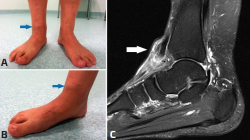

En estos pacientes, el tendón (y músculo) tibial anterior intenta frenar en contracción excéntrica esta caída libre hacia medial y plantar, pero sin éxito. Esta contracción excéntrica continuada es visible en el análisis de la marcha en consulta cuando el paciente camina acercándose al explorador. No es de extrañar que detrás de la mayoría de las roturas degenerativas del tendón tibial anterior exista un pie plano valgo de base(10,11) (Figura 1). Desde la posición de colapso, todos los tendones inversores, en acción concéntrica y en cadena cinética cerrada, tienen que crear una rotación externa de la tibia/pierna que consiga remontar el medio y antepié para poder finalizar con la propulsión durante el tercer rocker de la marcha.

Figura 1. En el contexto mecánico de un pie plano valgo, el tendón tibial anterior tiene que intentar frenar en acción excéntrica la pronación tarsiana. Con frecuencia sufre roturas degenerativas por este motivo. A: imagen clínica de un paciente con pies planos y rotura espontánea del tibial anterior. La flecha señala el muñón proximal del tendón en la región retinacular anterior del tobillo; B: imagen del mismo paciente en otra perspectiva en la que se objetiva mejor la pronación tarsiana patológica; C: imagen de la resonancia del paciente con la flecha señalando el muñón proximal del tendón tibial anterior.